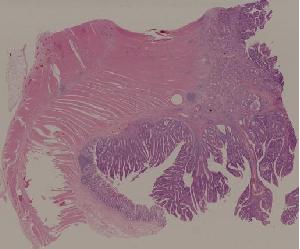

28. Adenoma of the colon